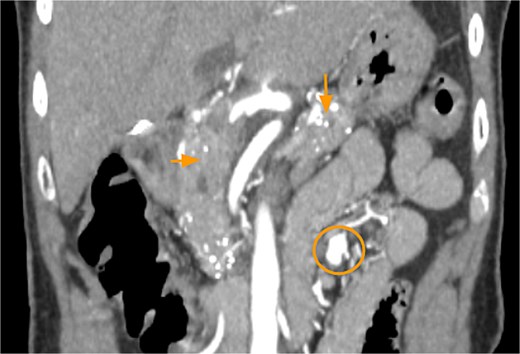

Laboratory evaluation revealed leukocytosis (12.87 × 109/l), elevated creatinine (1.29 mg/dl), and lipase of 79 U/l. CTA of the abdomen and pelvis showed a 1.2 cm pseudoaneurysm arising from a distal SMA branch and pancreatic calcifications consistent with chronic pancreatitis (Fig. 1).

CTA abdomen and pelvis demonstrating pancreatic calcifications (arrows) and SMAP (circle).